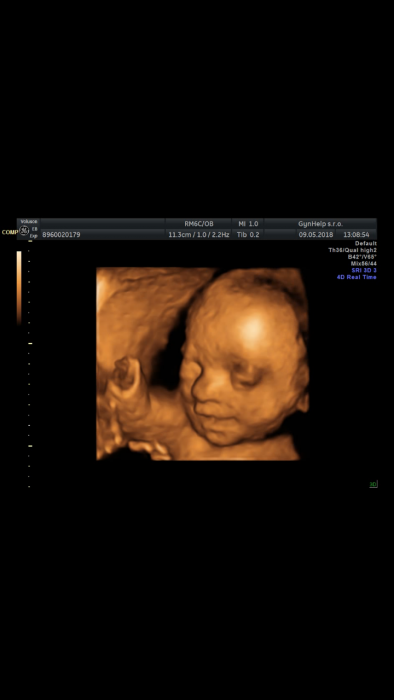

A holky co takhle nějaké utz fotky miminek? :) ja pridávám 4D Jonáše. Doktor si na posledni kontrole sam vzpomněl ze minule moc nespolupracoval a udělal mi ještě jednu hezkou fotku.

Test na cukrovku ok. Rikal, ze me ceka nejdulezitejsi a nejvic nebezpecny mesic, at jsem opatrna. Fotecku taky poslu :-)